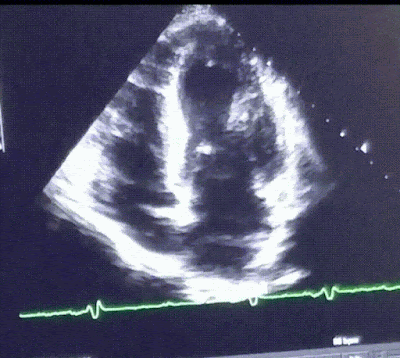

![]() |

هذا مخطط صدى القلب لرياضي لشخص يبلغ ة 30 عامًا يعاني من تضخم القلب.، |